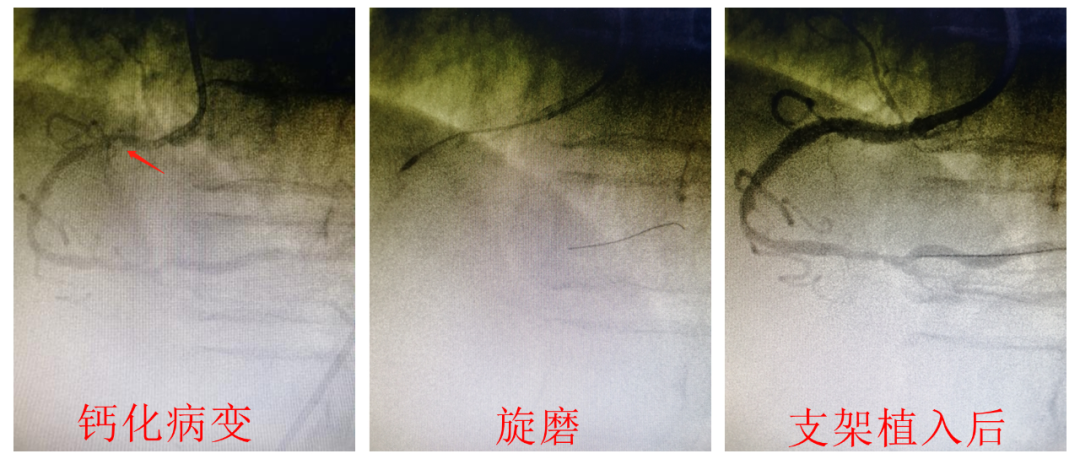

何鹏程院长了解患者情况后,立即组织科内讨论,经过仔细研究冠脉造影影像以及充分评估病情,考虑患者年龄大、体重低,外科搭桥风险极高,介入手术是唯一有效的选择。经过与患者家属积极沟通,家属很快同意介入手术方案。数天后,何鹏程院长带领心血管内科介入团队快速完成左冠病变支架植入后,立即对严重钙化右冠病变实施旋磨,由于做了细致的准备和全面的预案,针对手术过程中出现的血流不畅、心脏停跳等紧急情况,心内科团队都从容面对,高效处理,让患者转危为安,顺利完成了如此高难度高风险的介入手术,成功植入支架,达到了一次手术为患者严重三支血管病变实现完全血运重建的目标。术后患者血压、心律稳定,胸痛症状完全缓解,术后第3天已下床行心脏康复锻炼。